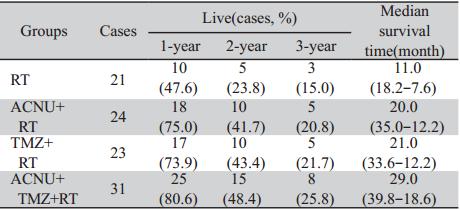

各组患者术后均定期复查头颅CT或MRI及血 常规,以了解患者手术后恢复及肿瘤复发情况, 术后定期行Karnofsky评分以评价患者术后的生存 质量。每周进行一次血常规检查,每隔4周检查 肝、肾功能及常规体检,以评价药物毒性和患者 耐受性,进行临床评价,以便调整用药,直至给 药结束为止。每4~6周复查头颅CT或者MRI检查 以判定肿瘤生长情况见图1~图3。不良反应以主观 症状和客观体征评价为主,按WHO标准分为0~Ⅳ 度。

A,B: enhanced MRI simulation before operation. There was an obvious enhancement with irregular margin in the left temporal lobe. C,D:enhanced MRI simulation 3 months after operation. There was no obvious enhancement in the left temporal lobe 图1 56岁男性间变性少突-星形细胞瘤(WHO Ⅲ级)患者手术前后增强MRI对比 Figure 1 Comparison of enhanced MRI simulation of a 56 years old male with anaplastic oligoastrocytoma(WHO grade Ⅲ)before and after operation |